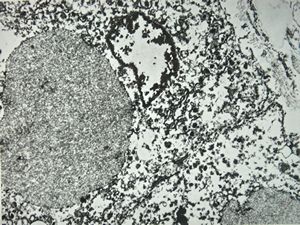

M,66y. | siderosomes

M,66y. | hemosiderin - siderosomes